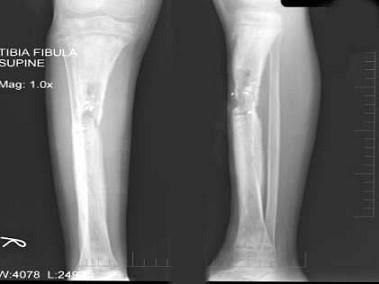

问题 女,12岁,右小腿肿胀,疼痛,发热3月余,摄片如图所示,下列征象哪项是错误的?(?)

选项 A.骨质呈溶骨性破坏 B.骨质增生硬化 C.骨膜呈层状增生不明显 D.可见软组织肿块 E.软组织肿胀

答案 D